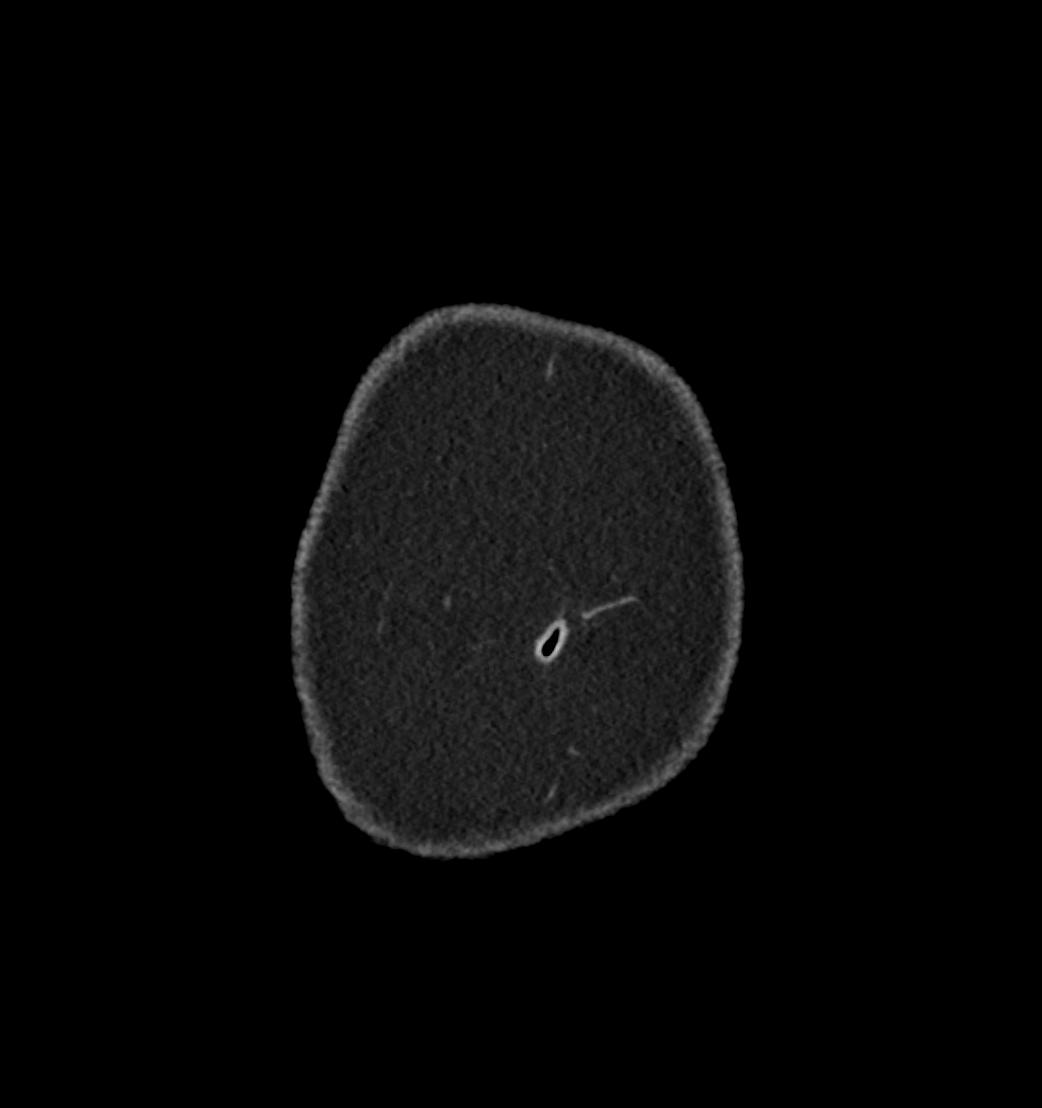

Patient: Padmakumar A. , *1988-04-24, PID: 3000069741773230809

Study Description: CT ABDOMEN

Image Series: Abdomen Cor 3mm [4]

<< Previous | Image 7 of 119 | Next >>